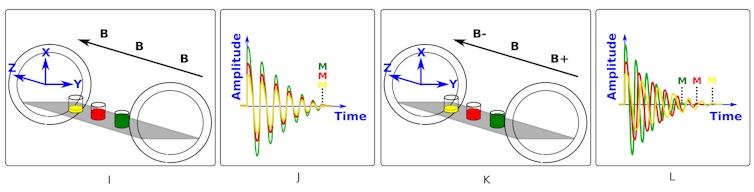

This is demonstrated in the diagrams below.

Figure I shows yellow, red and green glasses of water which represent the head, chest and abdomen of a patient in the scanner. We can see in figure I that the magnetic field - shown as B - is the same strength all along the z-axis. Figure J shows that after we “kick” the system, all three glasses of water respond by emitting radio waves of the same frequency. The signals have different amplitudes due to the different water levels.

Figures K and L show what happens if we make the field stronger at one end (B+) and weaker at the other (B-). We see in figure L that this gradient changes the Lamor frequency of the protons along the z-axis and the signals now have different frequencies.

So, by applying a magnetic field gradient and tailoring the frequency of the wave that “kicks” (excites) the protons we can select to only excite a thin slice of the patient.

Anyone who has had an MRI scan, will know that they are in the scanner for a significant length of time. This is because the patient has to be scanned slice-by-slice by applying the gradient and incrementing the frequency of the excitation. This is repeated many times to sequentially collect signals and build up an image from the slices of the patient.